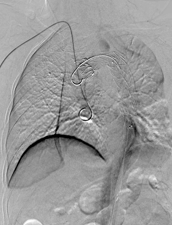

经过周密计划,该科室制定了分阶段杂交手术方案:心血管外科先通过2处5cm的手术切口行颈动脉—锁骨下动脉搭桥,建立血流通路;接着介入科团队接力,通过3处不超过1cm的微创伤口完成胸主动脉夹层腔内覆膜支架隔绝术,并用血管塞精准封堵左锁骨下动脉起始段以避免术后支架内漏。

△注:支架精准定位,稳定释放,成功以“人工血管”将主动脉破口隔绝。

整台手术历时7小时50分钟,术程中患者生命体征保持平稳,总出血量控制在50ml以内。这种复杂且高危的四级手术,单靠任何一个学科都难以完美完成。正是MDT团队的精诚合作,让患者在最小的创伤下获得了最有效的治疗。

△注:患者出院后定期我科门诊复查,术后2月复查提示支架完美重建胸主动脉血管通路,原夹层内部基本血栓化,未发现相关并发症。